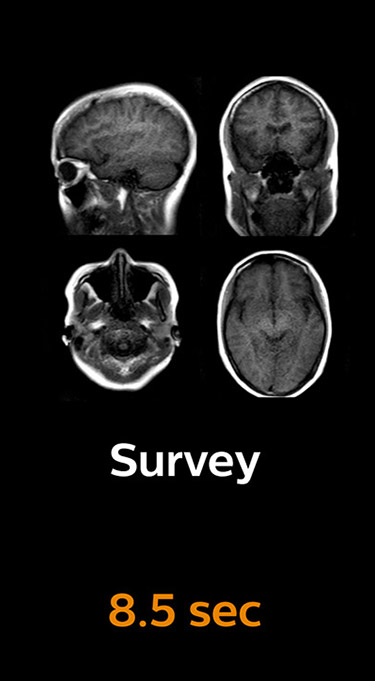

The most frequently used brain MRI examination at KNC included approximately 15 minutes of scanning time, and was quite comprehensive with fairly short scan times. When Compressed SENSE became available, its great impact on the brain exam quickly became clear.

Scanning time reduction in brain MRI with Compressed SENSE

With Compressed SENSE, the scan time for the routine brain examination at KNC was reduced from 15:48 to 10:19 minutes, which corresponds to 35% reduction.

Ingenia 3.0T CX

Scan time 15:48 min.

Brain with Compressed SENSE

Scan time 10:19 min.